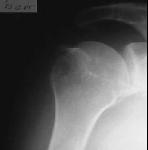

Рентгенография правого плечевого сустава от 01. 11.05. (Рентгенограмма № 1) :

выявляется нижний вывих головки плечевой кости, перелом большого бугорка плечевой кости со смещением отломка по ширине.

Заключение: Переломо-вывих головки плечевой кости правого плечевого сустава.

Заключение от 01.11.2005.: Переломо-вывих головки плечевой кости правого плечевого сустава.